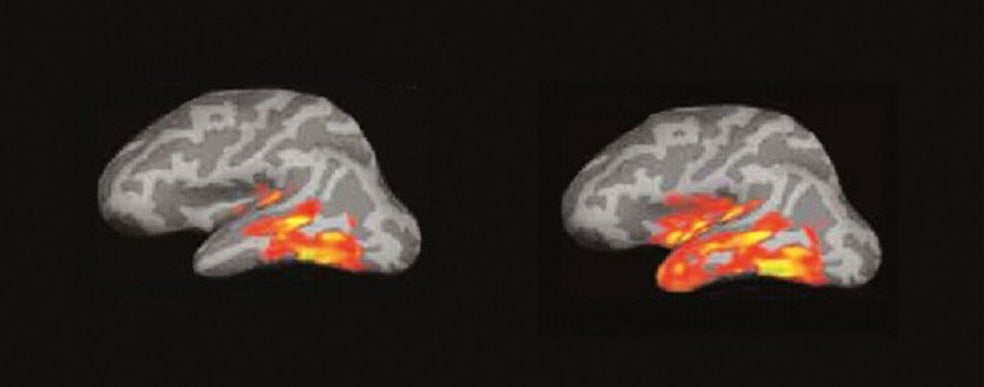

Para muchas personas, el tacto de las páginas o el peso del ejemplar entre las manos es una parte irrenunciable de la experiencia lectora. No hay e-book, tableta ni smartphone que puedan sustituir esa sensación. Pero son una minoría. Según el último barómetro de hábitos de lectura, publicado en 2018 por la Federación de Editores, solo el 40 por ciento de los lectores lee exclusivamente en papel. En realidad, los datos no hacen más que confirmar nuestros propios hábitos. Pero más allá del impacto que el libro digital ha tenido en el negocio editorial, pocos se han parado a pensar en cómo afecta a nuestra capacidad lectora el soporte que elegimos para disfrutar de una novela, un ensayo o un libro de autoayuda. Una de ellas es la neurocientífica cognitiva Maryanne Wolf, especialista en el cerebro lector y profesora de la Universidad de California en Los Ángeles, donde dirige el Centro de Dislexia, Estudiantes Diversos y Justicia Social. Autora de más de 170 artículos académicos y del superventas Cómo aprendemos a leer, su último libro es Lector, vuelve a casa: cómo afecta a nuestro cerebro la lectura en pantallas (Deusto Ediciones). Escrito como una compilación de cartas dirigidas a sus lectores, Wolf reflexiona sobre el impacto que las pantallas están teniendo en la lectura profunda, el análisis crítico y hasta en nuestra capacidad para empatizar con el prójimo. Pero también en el futuro de nuestras democracias…